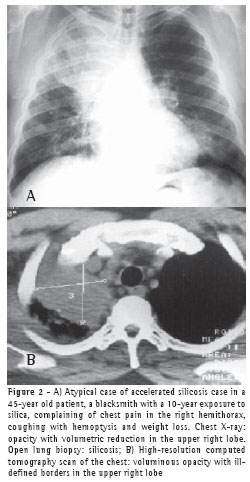

All 75 patients with accelerated silicosis were male. The mean age was 43 years (range, 28-76 years). The mean duration of exposure was 14.2 years (range, 7 months-38 years). Of the 75 patients, 62 (82.6%) were sandblasters, 11 (14.6%) were blacksmiths, 1 (1.4%) was a welder, and 1 (1.4%) was a metal polisher. In reference to concomitant tuberculosis, 39 patients reported a history of pulmonary tuberculosis (52%). Of those, 37 developed the disease during their exposure to silica.The diagnosis was confirmed in 31 cases: 24 through direct sputum smear microscopy; 3 through direct mycobacteria culture of the sputum; 1 through mycobacteria culture of the bronchoalveolar lavage fluid; and 3 through histopathology. In 8 patients, there was clinical and radiological suspicion of tuberculosis based on a response to specific treatment. The radiological classification of the large opacities seen on the chest X-rays was as follows: Type A in 23 patients (30.7%); Type B in 25 (33.3%); and Type C in 27 (36%) (Figures 1A and 1B). Of the cases analyzed, 74 presented bilateral conglomerate masses, whereas only 1 presented unilateral lesion (Figures 2A and 2B).

Of the 75 cases analyzed, only 1 presented a large unilateral opacity

mimicking a tumor. The diagnosis of silicosis was made via thoracotomy with open lung biopsy. Isolated PMF lesions are frequently mistaken for lung cancer. Given the higher incidence of lung cancer in these patients, it is important to take a diagnostic approach in order to effectively differentiate malignant pneumoconiosis lesions from benign ones.(19)